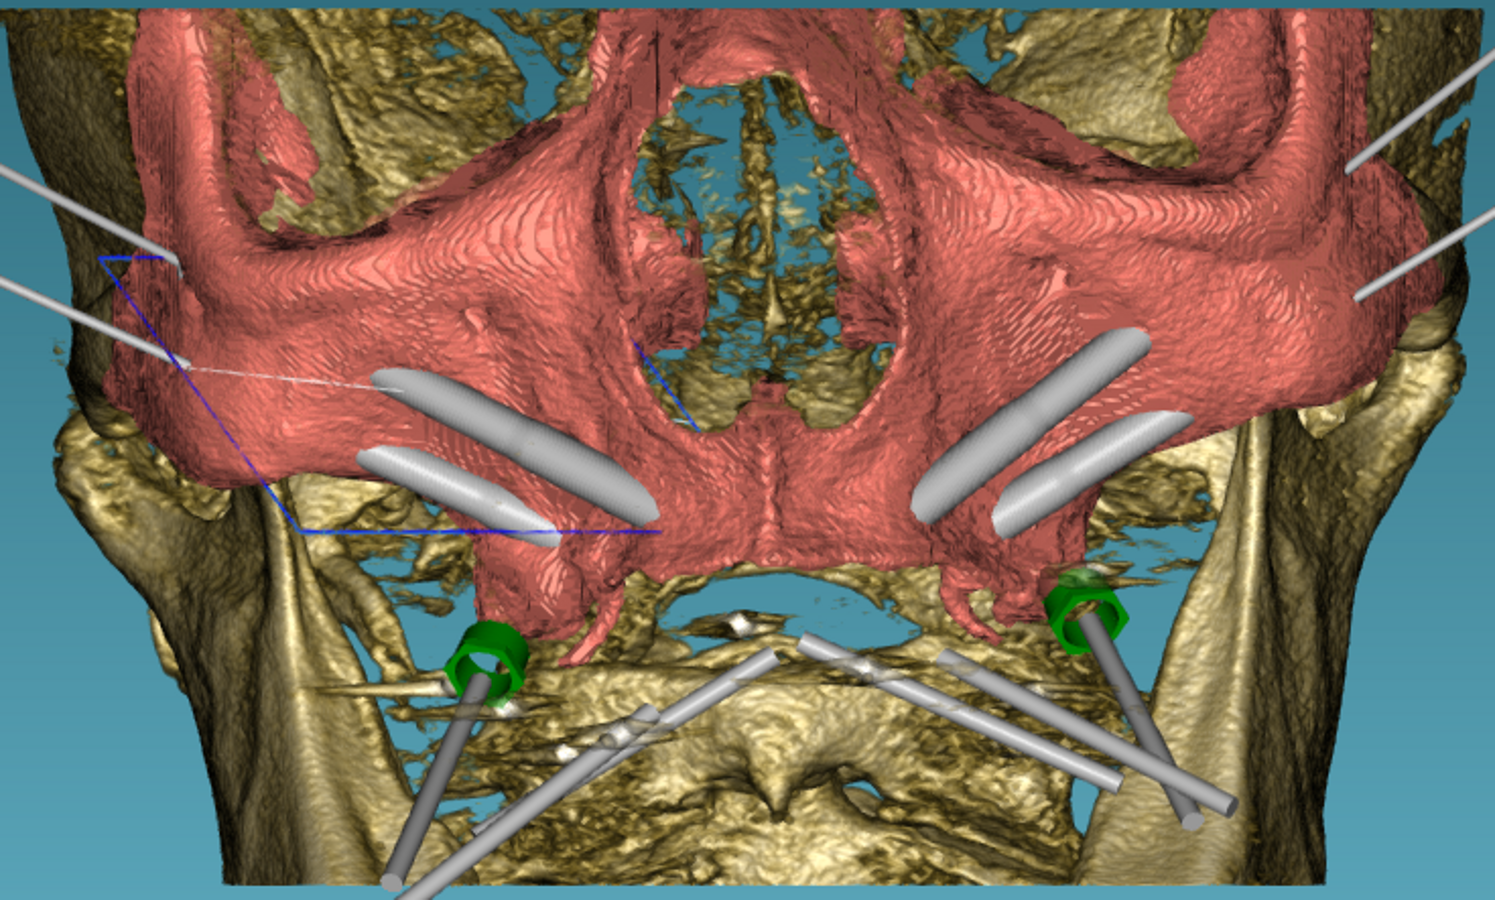

2. Diagnostiek en digitale behandelplanning

Gezien het extreem beperkte botvolume werd gekozen voor een vaste maxillaire rehabilitatie met een zygomatisch implantaatconcept, waarbij augmentatieve reconstructies werden vermeden. Met behulp van digitale planning in JDreal-software werden twee zygoma-implantaten en twee nasale/anterior-implantaten virtueel gepositioneerd (figuur 12). Op basis van deze planning werd een 3D metaal geprinte boormal ontworpen om een nauwkeurige, begeleide plaatsing volgens het geplande traject te kunnen garanderen.

Digitale planning van de implantaten (twee zygoma’s en twee nasale).